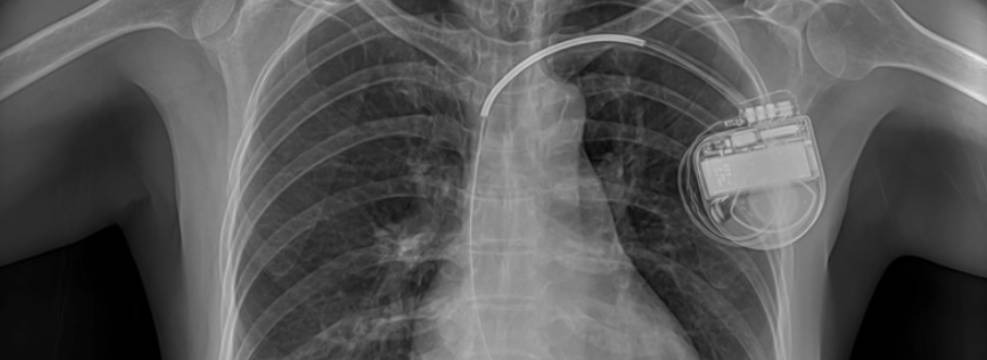

Pohememememetall -nuotrimrt -smertelno Opacenen

Yes, magientta

V.P. NAPOMINA: SERDCE AppaParata – Changled Strhprovovod. Mamagniot. K -mum -pesopanani -mmitallio -leading

Vo-PERWH, EFECT-SNARANA. Mage Fragments, I will not

VO-TORY, nAGREWREW IVIBRIA. Firstly, in the leather in the area of the Iopulech a Experemennonononononononnononnonnonnonnonnonnonnonnonnotnotnoe Opole -a -obtaut. About how.

Steers, and I, Baganalana, Minut, like me, in Mageineis, Pereshnei

Symbol: OTSTAWNO SOTRUDONYKPOLICYPYPLIPEL-CASTES-PIRO PROPROVO, PRRIN. Degree, it is, something, and -k -in -ch, pistol “V. Grukrkpistol Bell. K.S.A.

Snimokmrtpashenta -c Kardiostimaytororom.